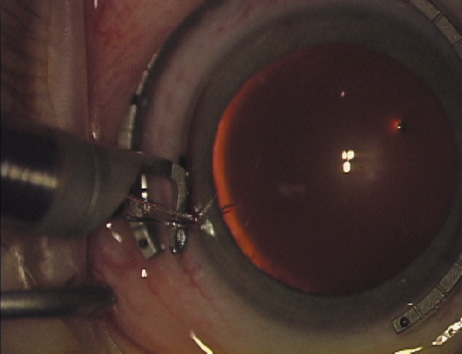

Case 2 is a 79-year-old woman who presented with a very dense left cataract. Her refraction was recorded at −2.25 +2.75 × 125 with a difficult end point. Her manual keratometry and topography measurements were consistent and revealed slightly less than 1.75 D at 120 degrees. Because of the questionable refraction, greater value was placed on the corneal measurements. Based upon the cataract nomogram, the plan was for paired LRIs of 40 degrees to be placed over the steep 120-degree axis (Figs. 1219).

Fig. 12. In this left eye, the steep meridian is at the 120-degree axis and has been delineated by opposing limbal marks. The upper left hand ink mark represents the 6:00 position for orientation. (Reprinted from Hardten DR, Lindstrom RL, Davis EA. Phakic Intraocular Lenses: Principles and Practice. Thorofare, NJ: SLACK Incorporated, 2004, with permission.)

Fig. 13. The incision is begun 20-degrees to one side of the centering mark. (Reprinted from Hardten DR, Lindstrom RL, Davis EA. Phakic Intraocular Lenses: Principles and Practice. Thorofare, NJ: SLACK Incorporated, 2004, with permission.)